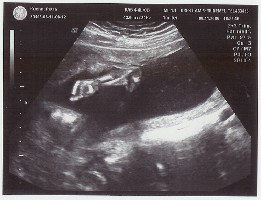

wir kommen gerade von der Feindiagnostik.

Leider hat es auch heute noch kein Outing gegeben.

Aber dafür sind alle sichtbaren Organe in Ordnung

und die Durchblutung ist super.

Es gab auch keine spektakulären Bilder,

aber ein Süßes habe ich angehängt.

Da hat das Würmchen uns voll zugewinkt.

auf dem Bild ist das Baby nicht zu sehen,

sondern nur der Arm.

Die Ärztin fand das so witzig,

weil das Kleine die Hand immer auf und zu gemacht hat.